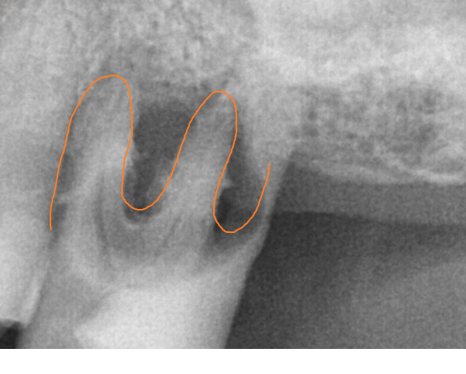

작은 x ray도 찍어보고

ct도 찍어 찍어 최대한 남길 수 있는 치아들은 남기고 싶었으나

아래 치아의 경우 몹시도 흔들리고 충치가 심하여

남아있는 치아 전부 제거가 필요했습니다.